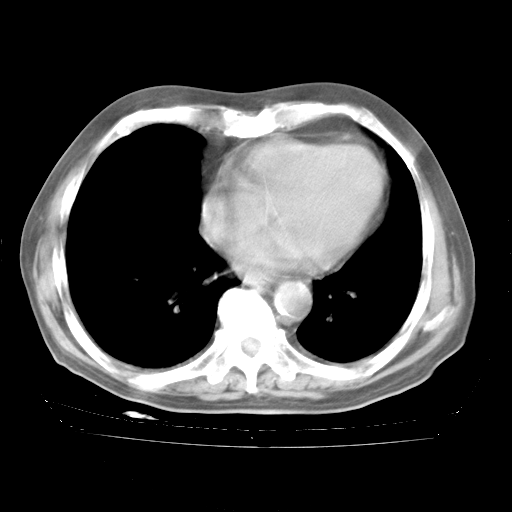

轻微咳嗽,无痰,(体温正常时)R20次/分,P75次/分,双肺底、腋下可闻及少量捻发音。下肢轻度浮肿。

ECG:右心室增大

心脏超声检查:无右心室增大。